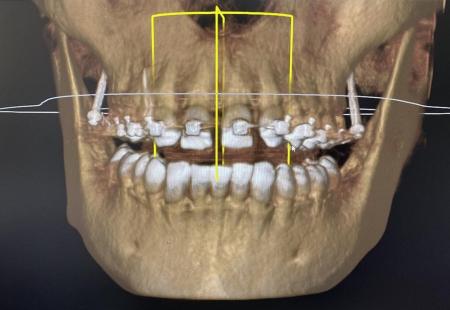

Тотальная реабилитация Пациента М.

- Ревизия очагов хронической инфекции в полости рта.

- Дентальная имплантация на нижней челюсти в области жевательной группы зубов.

- Дентальная имплантация на верхней челюсти в области жевательной группы зубов.

- Костная пластика (открытый синуслифтинг справа и слева) в области верхней челюсти справа и слева.

- Пластика мягких тканей в области имплантатов верхней и нижней челюсти.

- Временное протезирование (Жданов И.И) на верхней и нижней челюсти.

- Постоянное протезирование верхней и нижней челюсти. (Жданов И.И)